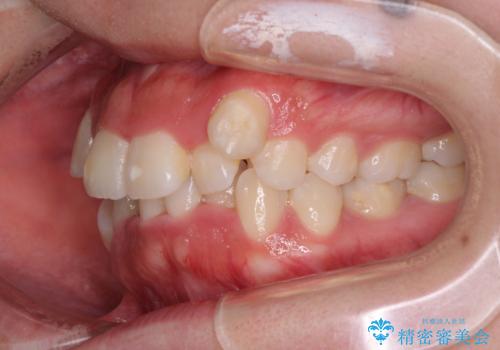

- 上下の八重歯やデコボコを気にして来院された患者様です。

上下ともに八重歯が顕著であったので、上下左右第一小臼歯4本を抜歯し、補助装置を使用して速やかに改善しながら、ワイヤー装置にて矯正治療を行うこととしました。

気になっていた八重歯は装置装着から3か月ほどで解消されました。

2年以内を目標として治療を開始しましたが、1年半ほどで終えることができました。